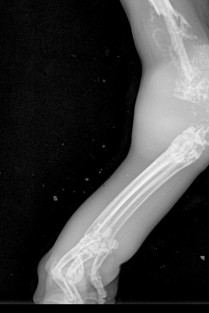

Après avoir présenté les examens radiographiques du thorax puis de l’abdomen dans le cadre de ses soirées, l’AFVAC Ile-de-France vous propose cette année " La radiographie du squelette appendiculaire : les règles d’or de l’interprétation ", en visio-conférence.

- connaitre la sémiologie radiographique osseuse ;

- avoir une approche radiographique systématisée et rigoureuse ;

- apprendre à établir un diagnostic différentiel à la suite de l’interprétation radiographique ;